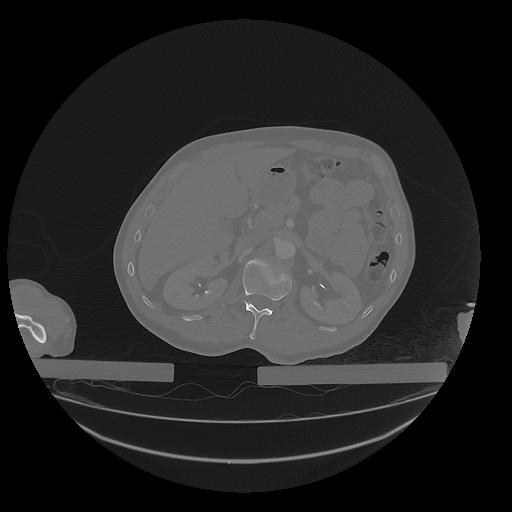

31 PULMON,CE,Vol,1.0,PULMON,,